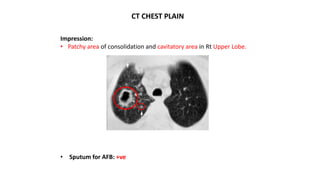

CT CHEST PLAIN

Impression:

• Patchy area of consolidation and cavitatory area in Rt Upper Lobe.

• Sputum for AFB: +ve